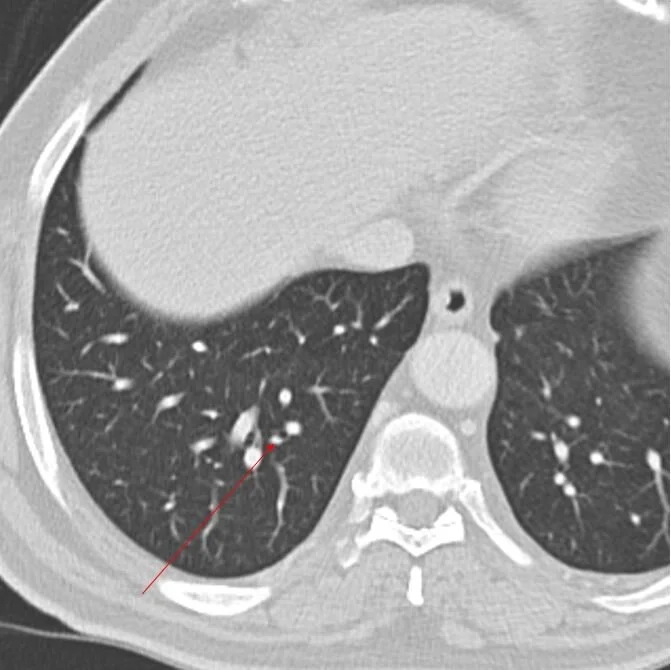

CT 2 years after nephrectomy. Tint RLL lung nodule.

Followup CT 1 year later, nodule is larger. This was oligometastasic disease.